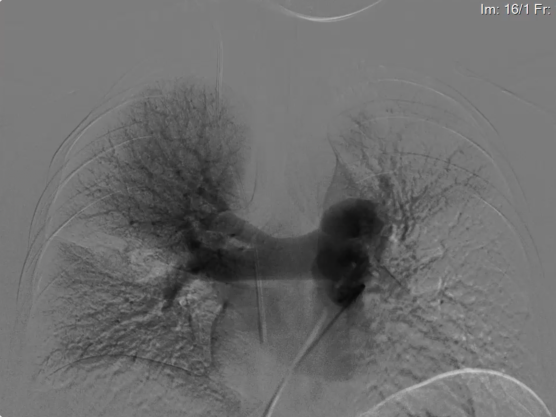

专家团队将Tendvia®血栓抽吸导管,沿导丝推送至左侧肺动脉,管口贴近血栓处停止,撤出导管芯。并将Tendvia®肺动脉取栓支架沿导丝通过抽吸导管向前推送,精确导入到患者的左侧肺动脉血栓部位。

再回撤输送鞘管,支架自动膨开,等待90秒,连接抽吸器并形成负压,回撤取栓支架的同时旋转开关释放负压,最后,Tendvia®肺动脉取栓支架捕获和收集血栓进入抽吸导管,经负压抽吸同步的作用下,顺利为患者取出左侧肺动脉血栓。

经过1个多小时的奋战,复查造影提示:左肺动脉干充盈缺损较前明显减少,血流通畅。患者胸闷症状立即得到缓解,血氧饱和度迅速回升,成功取出大部份血栓。